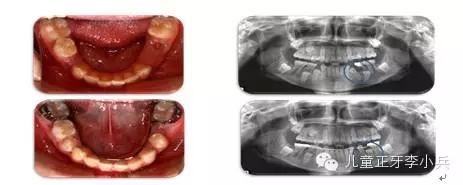

4.III類(lèi)骨性畸形的早期矯治:傳統(tǒng)的功能矯形概念是在兒童青春發(fā)育高峰前期開(kāi)始。對(duì)于骨性III類(lèi)的矯形治療的開(kāi)始時(shí)間,國(guó)內(nèi)外一直存在爭(zhēng)議。華西兒童早期矯治專(zhuān)科在總結(jié)本科III類(lèi)骨性矯治的療效后,認(rèn)為III類(lèi)骨性的矯形矯治在第一橫磨牙萌出時(shí)(6歲)開(kāi)始必在青春發(fā)育高峰前期(9歲)時(shí)開(kāi)始能得到更多的骨性改變。(圖5,III類(lèi)骨性的早期功能矯形治療)必須強(qiáng)調(diào)的是,早期功能矯形治療必須保持到恒牙列初期(12歲)以維持矯形治療的效果,避免由于遺傳的影響造成的矯形治療的復(fù)發(fā)。43.webp.jpg

圖 5 骨性III類(lèi)錯(cuò)合的早期矯治,保持持續(xù)到兒童發(fā)育結(jié)束;